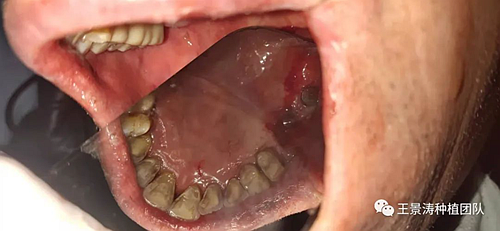

術(shù)后一周的口內(nèi)照片